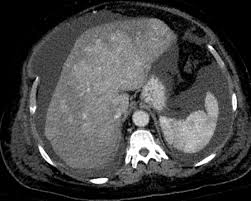

Chiasmata -mə-tə or chiasmas also chiasms 1. Esophageal varices are extremely dilated sub-mucosal veins in the lower third of the esophagus. Located in metro Denver northern Colorado and western Nebraska serving all of the Front Range our team consists of board-certified and fellowship-trained interventional radiologists. This results in hepatic congestion similar to Budd-Chiari syndrome and post-sinusoidal portal hypertension. The patients condition should be monitored throughout the procedure. They are most often a consequence of portal hypertension commonly due to cirrhosis. Toxic injury to liver sinusoids causes sloughing of endothelial cells that embolize to hepatic venules and cause eventual fibrosis of the venules. Coin in the Esophagus. There is no clear consensus regarding the number of occluded veins some authors claim that there should be at least one occluded hepatic vein 7 others state that there are no significant.

Carcinoma of the Colon. Budd-Chiari syndrome a blockage in one or more veins that carry blood from the liver back to the heart. And coumarin skin necrosis adrenal gland hemorrhage and infarction. Toxic injury to liver sinusoids causes sloughing of endothelial cells that embolize to hepatic venules and cause eventual fibrosis of the venules. Chiari malformation CM is a structural defect in the cerebellum characterized by a downward displacement of one or both cerebellar tonsils through the foramen magnum the opening at the base of the skull. Embolism and thrombosis of. La présence dune ou plusieurs affections prothrombotiques est fréquente La prise en charge repose sur un traitement anticoagulant précoce le traitement de l.